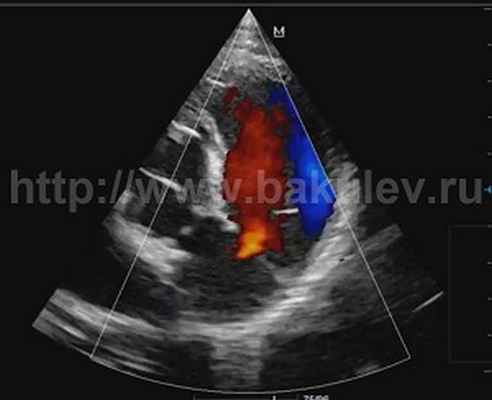

По данным ЭКГ были выявлены изменения, подтверждающие нарушение функции правого желудочка, обусловленные данной регургитацией. Электрический импульс по нему проходил более длительное время вследствие его гипертрофии и увеличения объёма, что выражалось в удлинении комплекса QRS до 125 мс (норма до 80 мс; риск внезапной смерти >180мс). При выполнении эхокардиографии наличие регургитации на клапане лёгочной артерии было подтверждено. Обратный поток крови из легочных артерий в момент расслабления правого желудочка имел умеренную вторую степень (Рис. 1 и 2).

Рис. 2 — ЭхоКГ до операции